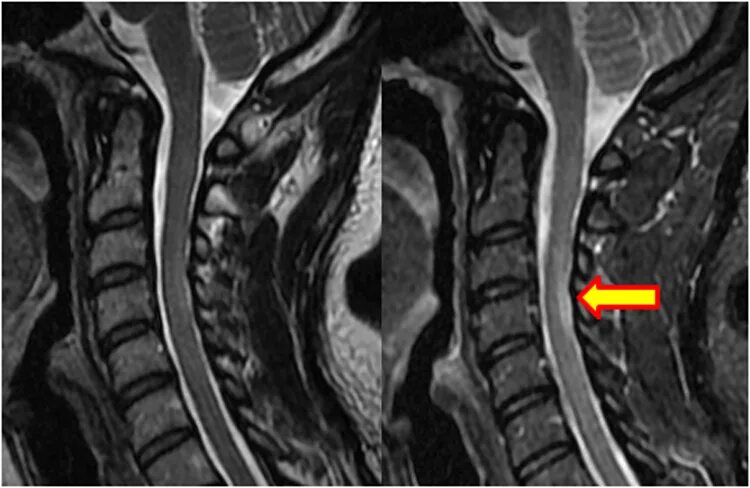

Bypass mrt